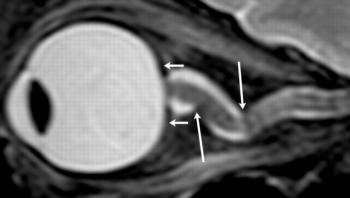

The results showed that, compared to short-duration astronauts, long-duration astronauts had significantly increased post-flight flattening of their eyeballs and increased optic nerve protrusion. Long-duration astronauts also had significantly greater post-flight increases in orbital CSF volume, or the CSF around the optic nerves within the bony cavity of the skull that holds the eye, and ventricular CSF volume—volume in the cavities of the brain where CSF is produced. The large post-spaceflight ocular changes observed in ISS crew members were associated with greater increases in intraorbital and intracranial CSF volume.

Over the last decade, flight surgeons and scientists at NASA began seeing a pattern of visual impairment in astronauts who flew long-duration space missions. The astronauts had blurry vision, and further testing revealed, among several other structural changes, flattening at the back of their eyeballs and inflammation of the head of their optic nerves. The syndrome, known as visual impairment intracranial pressure (VIIP), was reported in nearly two-thirds of astronauts after long-duration missions aboard the International Space Station (ISS).

"If the ocular structural deformations are not identified early, astronauts could suffer irreversible damage," he noted. "As the eye globe becomes more flattened, the astronauts become hyperopic, or far-sighted."